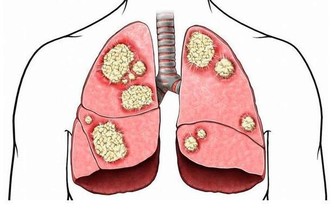

糖除了會增加熱量,還會為肝臟增添負擔。研究人員發現,含糖豐富的飲食與血液和肝臟中的脂肪含量升高有一定的關聯。不止一項研究表明攝入大量糖分會改變脂肪代謝,從而增加患心血管疾病的風險。肝臟中有過多的脂肪堆積是不健康的,高脂肪的人群中有大部分的人患有非酒精性脂肪肝。

結果發現,高糖飲食的非酒精性脂肪肝患者脂肪代謝過程發生了變化,這些變化帶來的後果是患心髒病或者中風的風險更大了。原本肝臟脂肪含量較低的男性在一段時期的高糖飲食過後,肝臟脂肪含量有所升高,其體內脂肪代謝發生了類似於非酒精脂肪肝患者的變化。研究得出的結論是,攝入過量的糖會改變脂肪代謝,增加患心髒病的風險,即使只是一小勺糖,只要超過了正常攝入量,對人的影響就可能是致命的。